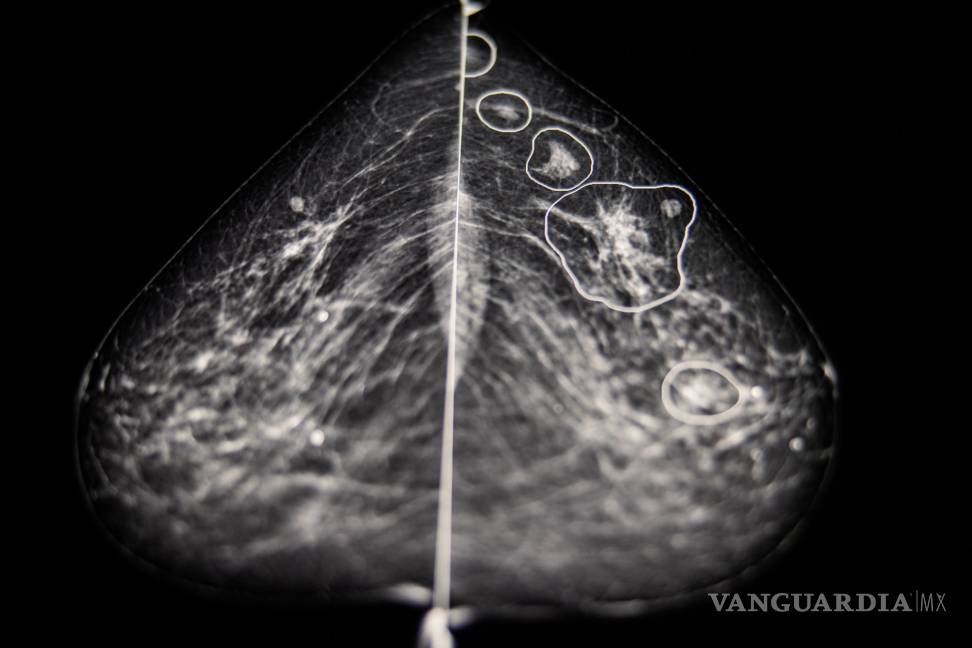

En el interior de una habitación oscura del Hospital del Condado de Bács-Kiskun en la periferia de Budapest, Éva Ambrózay, una radióloga con más de veinte años de experiencia, observaba un monitor de computadora que mostraba la mamografía de una paciente.

Dos radiólogos ya habían dicho que la radiografía no mostraba ningún signo de que la paciente tuviera cáncer de mama. Pero Ambrózay observaba atentamente varias zonas del escáner marcadas en rojo, que el programa de inteligencia artificial había señalado como potencialmente cancerosas.

“Esto es algo”, dijo. Enseguida ordenó que se volviera a llamar a la mujer para hacerle una biopsia, que se realizaría la semana siguiente.

A partir de los millones de casos que recibe el sistema, la tecnología crea una representación matemática de las mamografías normales y las que presentan cáncer. Gracias a su capacidad para analizar cada imagen de manera más detallada que el ojo humano, compara esa referencia para detectar anomalías en cada mamografía.

El año pasado, después de hacer pruebas con más de 275 mil casos de cáncer de seno, Kheiron informó que su programa de inteligencia artificial igualaba el desempeño de los radiólogos humanos cuando se usaba para una segunda interpretación. Además, reducía la carga de trabajo de los radiólogos en al menos un 30 por ciento, ya que disminuía el número de radiografías que tenían que leer. En otros resultados obtenidos el año pasado en una clínica húngara, la tecnología aumentó la tasa de detección de cáncer en un 13 por ciento porque se identificaron más tumores malignos.

En el Hospital del Condado de Bács-Kiskun en la periferia de Budapest, Ambrózay comentó que al principio dudó de la tecnología, pero se convenció muy poco tiempo después. Mostró la radiografía de una mujer de 58 años con un pequeño tumor detectado por la inteligencia artificial que a Ambrózay le costaba ver.

Esta tecnología identificó algo, dijo, “que pareció salir de la nada”.